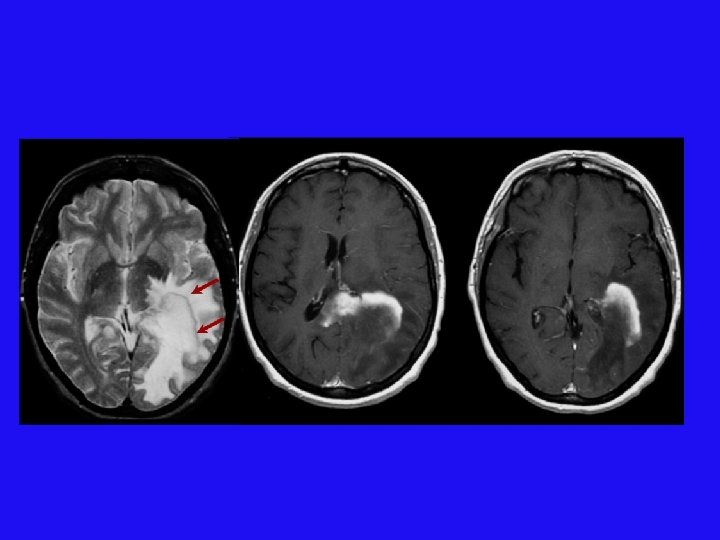

胶母 MR imaging and CT findings in 54 -year-old woman with glioblastoma. A, Axial T 2 -weighted and, B, contrast-enhanced axial T 1 -weighted MR images show a round cystic mass with complete rim enhancement and peritumoral edema in the subcortical white matter of the right frontal lobe. The signal intensity of the rim is isointense to gray matter on the T 2 -weighted image (arrow). C, Unenhanced axial CT image demonstrates isoattenuation (grade 2) of the rim (arrowhead).

胶母 Glioblastoma Multiforme: no dark line of advancing demyelination